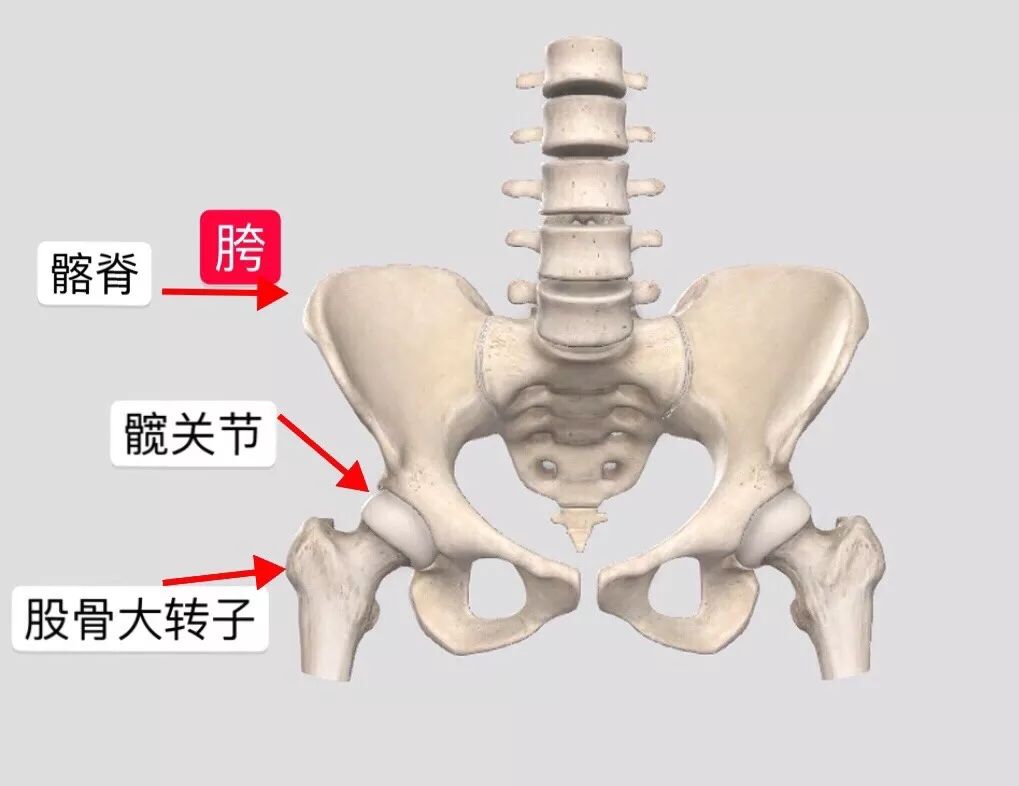

胯骨图片

股骨头是人体关节的一个组成部分,呈圆形,也就是我们通常所说的"胯骨

骨骼日记之髋骨 简介: 髋骨为不规则骨,由髂骨,耻